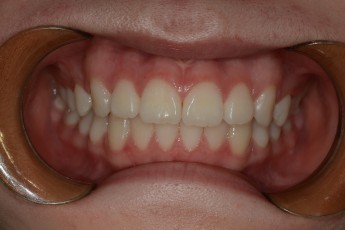

Before

After